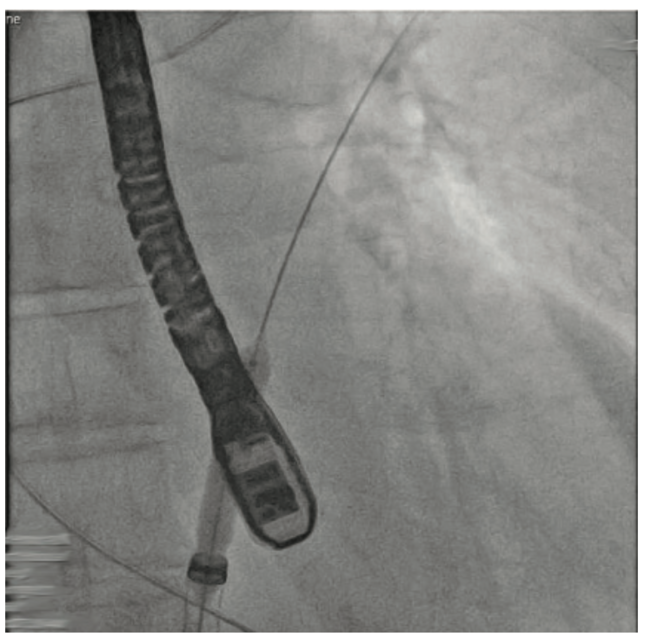

Crossing the interatrial septum was challenging. Although we were able to cross the interatrial septum with a transseptal needle, advancing the sheath across the fossa ovalis was difficult. Several maneuvers such as rotating and redirecting the sheath were not successful. Pre-dilation of the septum with 5 mm x 40 mm balloon did not allow for insertion of the MitraClip guide across the interatrial septum. At this point, we elected to use the balloon-assisted tracking (BAT) technique. Using a 7 mm x 40 mm balloon that was inflated to 10 atmospheres (atm) at the tip of the guiding catheter, we were able to advance the sheath through interatrial septum (Figures/Videos 1-3). Subsequently, a G4 XTW MitraClip was successfully deployed in the central position. A post procedure transesophageal echocardiogram showed mild mitral regurgitation.

Video 3. MitraClip prior to deployment.

Transseptal access is essential for many procedures including transcatheter mitral valve interventions, pulmonary vein isolation, left atrial appendage closure, and percutaneous left ventricular assist devices. However, there are many scenarios that one might face that can make transseptal access challenging. These include but are not limited to difficult engagement of the fossa ovalis, needle advancement, and sheath and guide advancement.1 In our case, MitraClip guide advancement was challenging. We were able to overcome this using the BAT or the ‘inchworming’ technique. This technique was originally described to overcome tortuosity, or a small-caliber or spastic radial artery during a transradial approach.2 We describe a new implication for the inchworming technique. The conical shape of the inflated balloon provides flexibility, minimizes trauma, and allows atraumatic transseptal access.